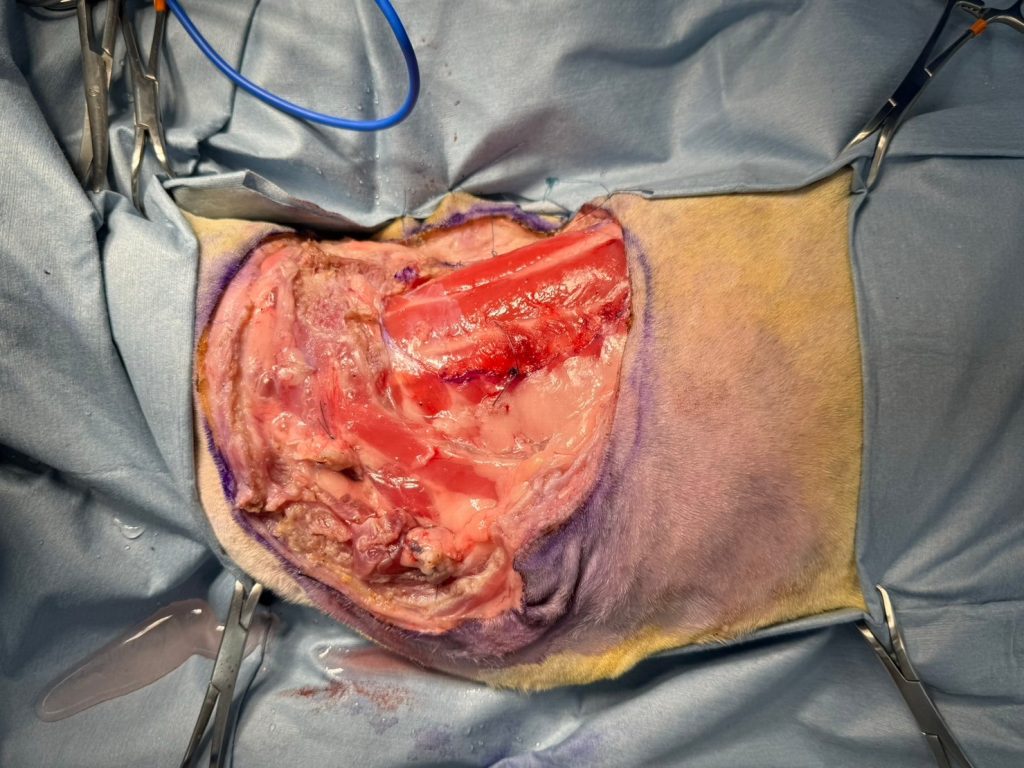

處理肩胛骨前緣:

使用超音波刀,沿著肩胛骨邊緣切斷其上的斜方肌、肩胛橫肌。

接著處理肩胛骨背側: 切斷第一層斜方肌,再切第二層菱形肌。

此時可把肩胛骨稍微抬起來,切除部分厚度的腹鋸齒肌。

繼續往下切除腹鋸齒肌

已經可以看到下一層的背鋸齒肌,以及隱約看近肋骨,代表接下來要開始小心行動了。

處理肩胛骨後側及衍伸的球狀腫瘤區(腫瘤2號),以已畫定的安全邊界切斷斜方肌、闊背肌,一路往腹部切,直到接近肱骨。

處理肩胛骨內側:

繼續切除部分厚度的腹鋸齒肌,看到腋窩神經叢和血管後 以縫線綁緊,再以超音波刀切斷。

至此「肩胛骨與腫瘤」已徹底與身體分離。

處理身體和肱骨相連的肌肉:

這部分因為沒有腫瘤,所以事情單純許多。切斷肱骨後側的闊背肌;切斷肱骨前側的鎖骨肱肌;切斷肱骨內側的深&淺胸肌。

至此,前肢已完全與身體分離。

在脊上肌群與腫瘤貼近的區域,移除一層肌膜。